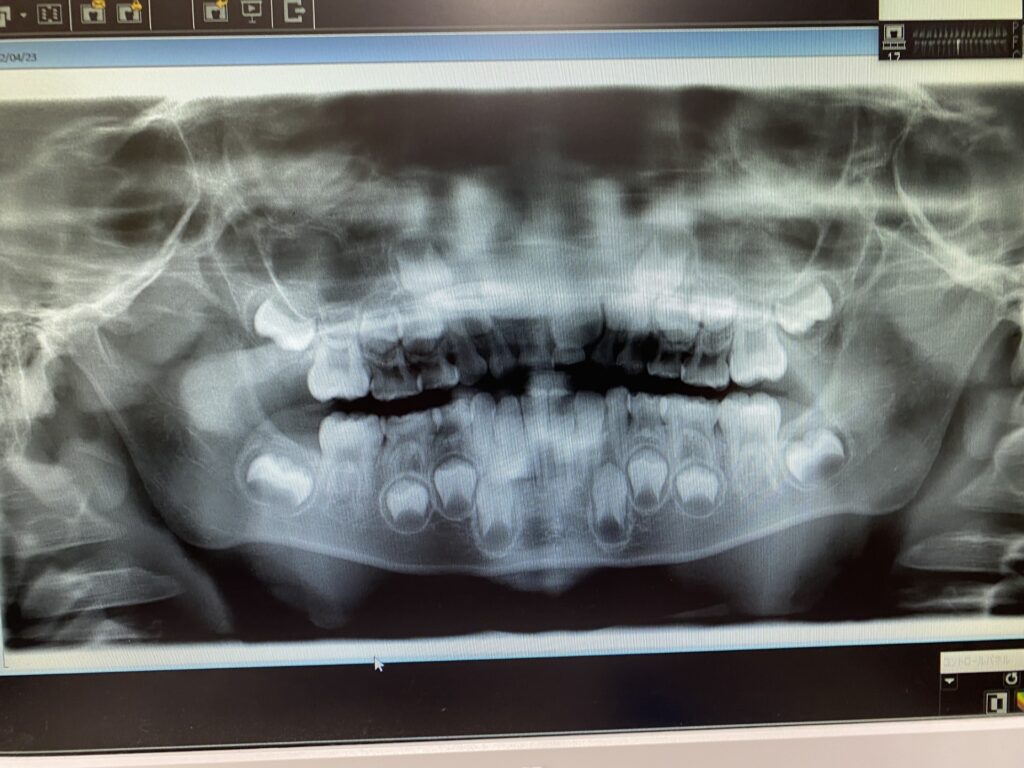

視診や触診、レントゲン画像(初診時には大きな歯列を確認できるものなど)をもとに、原因を診断をしてお話いたします。

レントゲン写真や口腔内写真を歯科治療ユニット前の大きな画面に映し、今後の治療方針についてわかりやすく丁寧にご説明申し上げます。質問事項などございましたらお話ください。治療のご了承を得られてから次の治療に進みます。